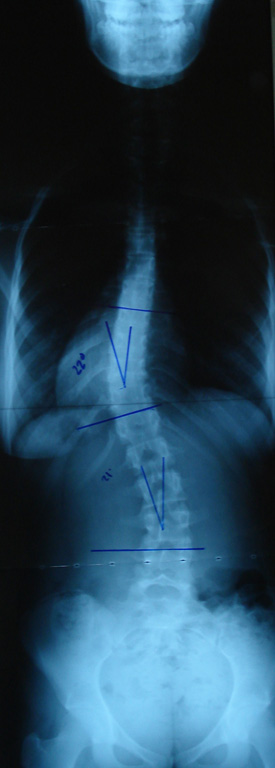

Grafilerle Skolyoz